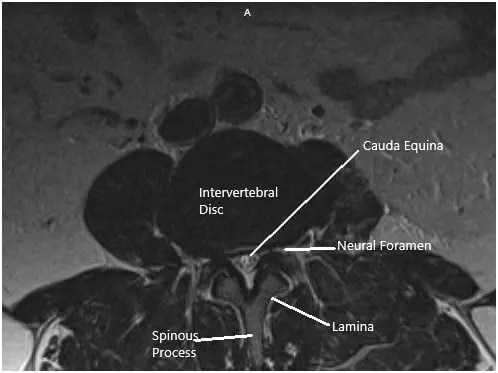

MRI suggested Ligamentum flavum hypertrophy contributing to severe central spinal stenosis at L2-L3. There was mild to moderate narrowing of the left neural foramen. There was a severe narrowing of the right neural foramen with effacement of the exiting right L2 nerve root due to a far lateral disc herniation.

At L3/4 there was a disc bulge and a facet and ligamentum flavum hypertrophy contributing to severe central spinal stenosis. There is mild to moderate narrowing of the bilateral neural foramina.

MRI of the Lumbosacral spine in sagittal and axial sections.